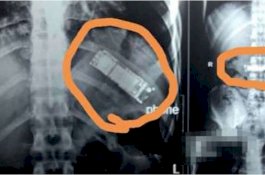

Awalnya Bercanda Telan Ponsel, 7 Bulan Kemudian Baru Bisa Dikeluarkan dari Perut

News

- 27 September 2020 09:02